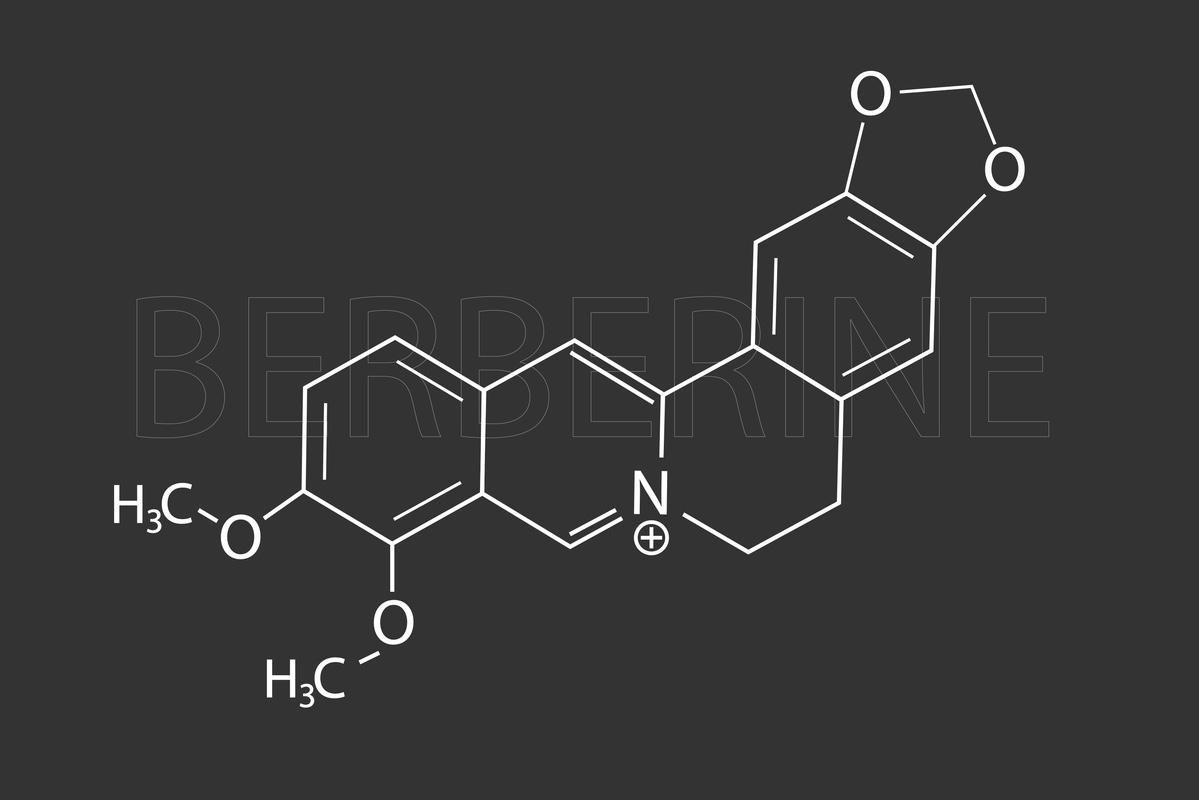

- NICOLAS MESSYASZ/SIPA

Ces derniers mois, plusieurs études ont fait état des effets néfastes du bisphénol A et les risques potentiels pour les femmes enceintes. Cependant, ce produit n’est pas le seul à représenter un danger pour la santé de la mère ou du bébé. Une récente étude publiée dans la revue Epidemiology, révèle que l’exposition à deux phénols, le triclosan et les parabènes peuvent perturber la croissance du bébé in utero et pendant les trois premières années de sa vie.

Les résultats négatifs observés sur la croissance de l’enfant par les chercheurs, ne mettent pas en cause le bisphénol A mais deux autres types de phénol : le triclosan, que l’on trouve dans les cosmétiques et les parabènes présents dans des produits d’hygiène tels que le savon ou le dentifrice. Les chercheurs ont constaté que les parabènes sont à l’origine d’une augmentation de poids à la naissance de l’enfant, puis à ses 3 ans. Les auteurs de l’étude rappellent qu’une croissance accélérée durant les premières années de vie d’un enfant présente un risque d’obésité plus accru dans les années à venir. L’exposition aux parabènes serait donc néfaste pour le développement morphologique du petit garçon.